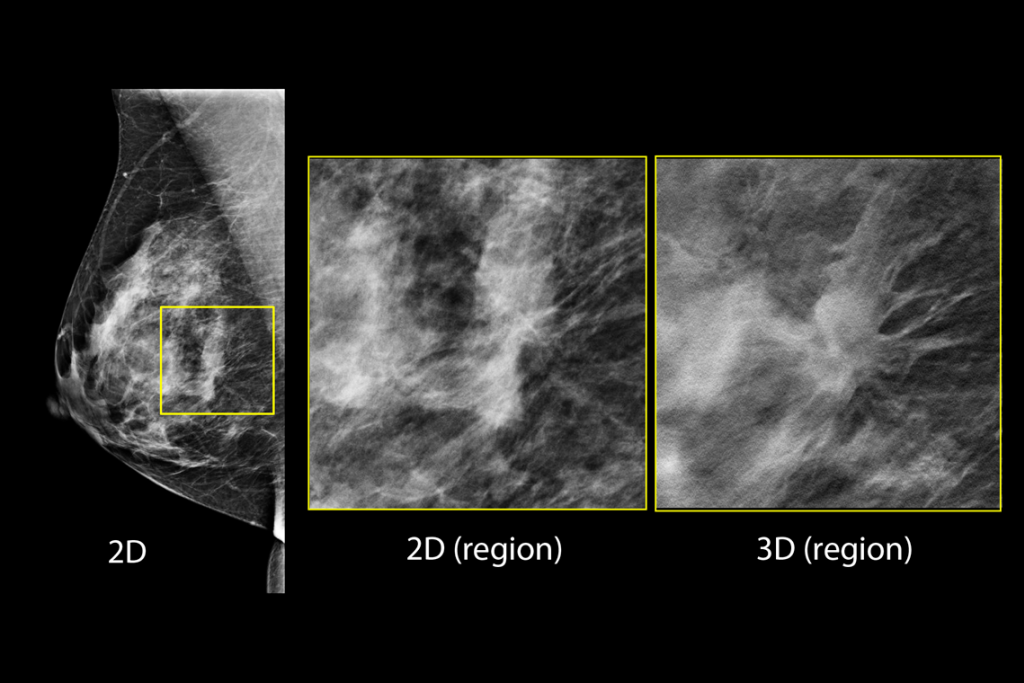

Clinical Images